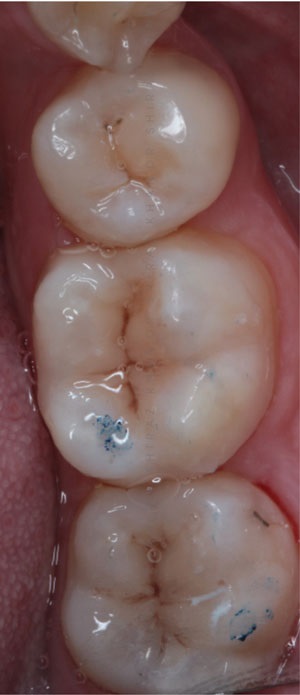

A 28-year-old patient attended the dental surgery for the first time in around 10 years. After using systematic desensitisation to help her overcome her fear, the patient began her restorative work. The patient had a tooth that had been previously restored with amalgam adjacent to another tooth which had never been restored. Whether or not a tooth has previously been restored does not indicate whether a tooth is suitable for a composite resin restoration. Both had clinical and radiographic caries and the probe was catching in the patient’s central fissure (Fig. 1).

• Figure 1